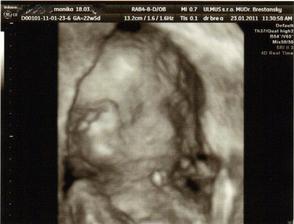

✿♥♥♥♥Bude to dievčatko!!!!! ♥♥♥♥✿

Bude to Stella 🙂

krasne 3D sono 🙂